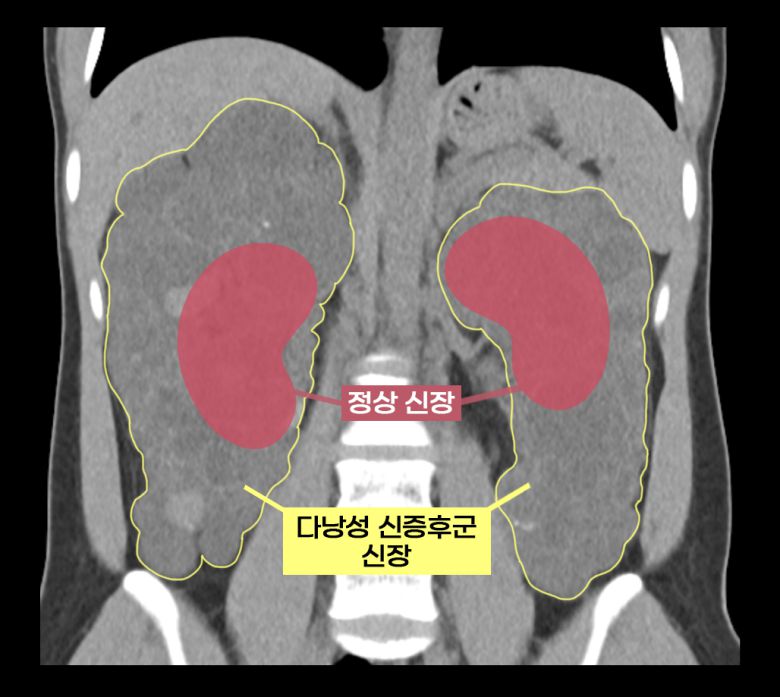

이 씨는 상염색체 우성 다낭성 신증후군을 앓았다. 다낭성 신증후군은 신장에 셀 수없이 많은 낭종이 발생해 신장이 최대 축구공만큼 커지는 유전 질환이다. 1000명 중 한 명꼴로 비교적 흔하게 발생하며 대부분 만성 신부전으로 이어진다.

보통의 만성 신부전 환자는 신장이식을 할 때 기존 신장을 그대로 두지만, 다낭성 신증후군 환자는 기존 신장을 떼어내야 한다. 이미 신장이 비대해진 상태이므로 새로운 신장이 들어올 공간을 확보해야 할 뿐만 아니라, 낭종 감염과 낭종 파열로 인한 출혈, 신장암 발병 등의 합병증 위험이 있어 양측 신장을 제거하고 신장이식을 진행한다.